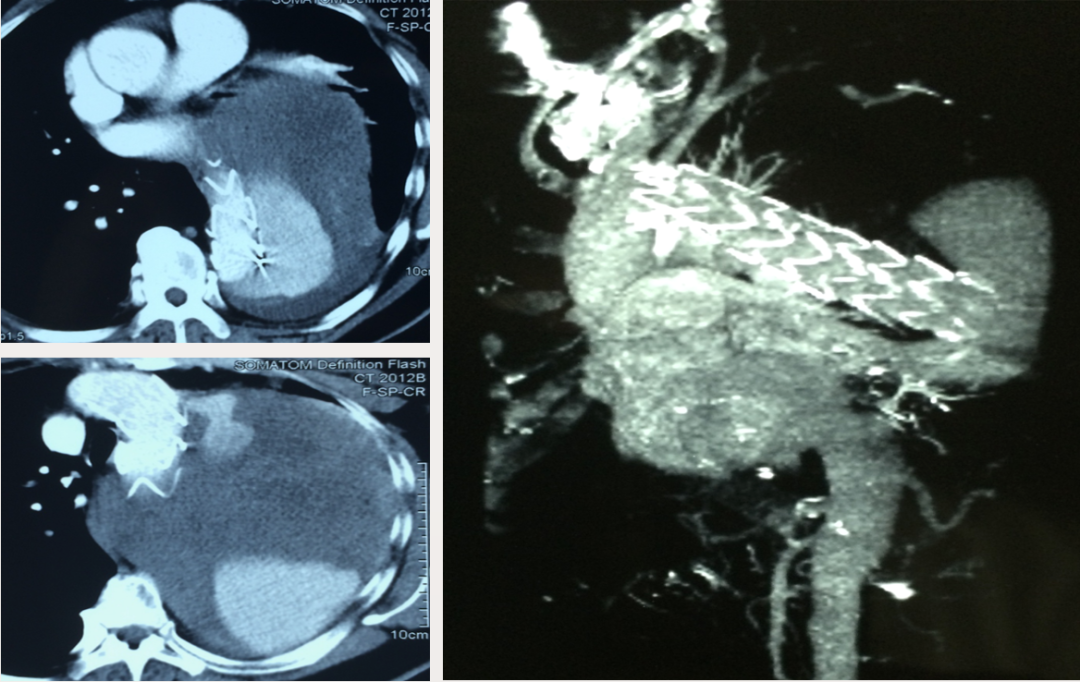

男性,44岁,慢性B型夹层。2010年12月行TEVAR术。

2013年5月发现RTAD,未处理。2015年2月死亡。

▎病例二

男,52岁,慢性夹层。2015年8月入院,4年前曾因B型层行TEVAR术,主动脉解剖变异,扭曲。行双烟囱+TEVAR术。术后第3天RTAD ,死亡。

▎病例三

男,60岁,慢性夹层。2013年12月行Debranching+TEVAR术 。2016年7月复查: RTAD ,未手术。失访。

▎病例四

男, 49岁,急性夹层 。2018年11月TEVAR。一月后复查:RTAD 。 2019年1月双开窗。2019年4月2日 复查,结果良好。